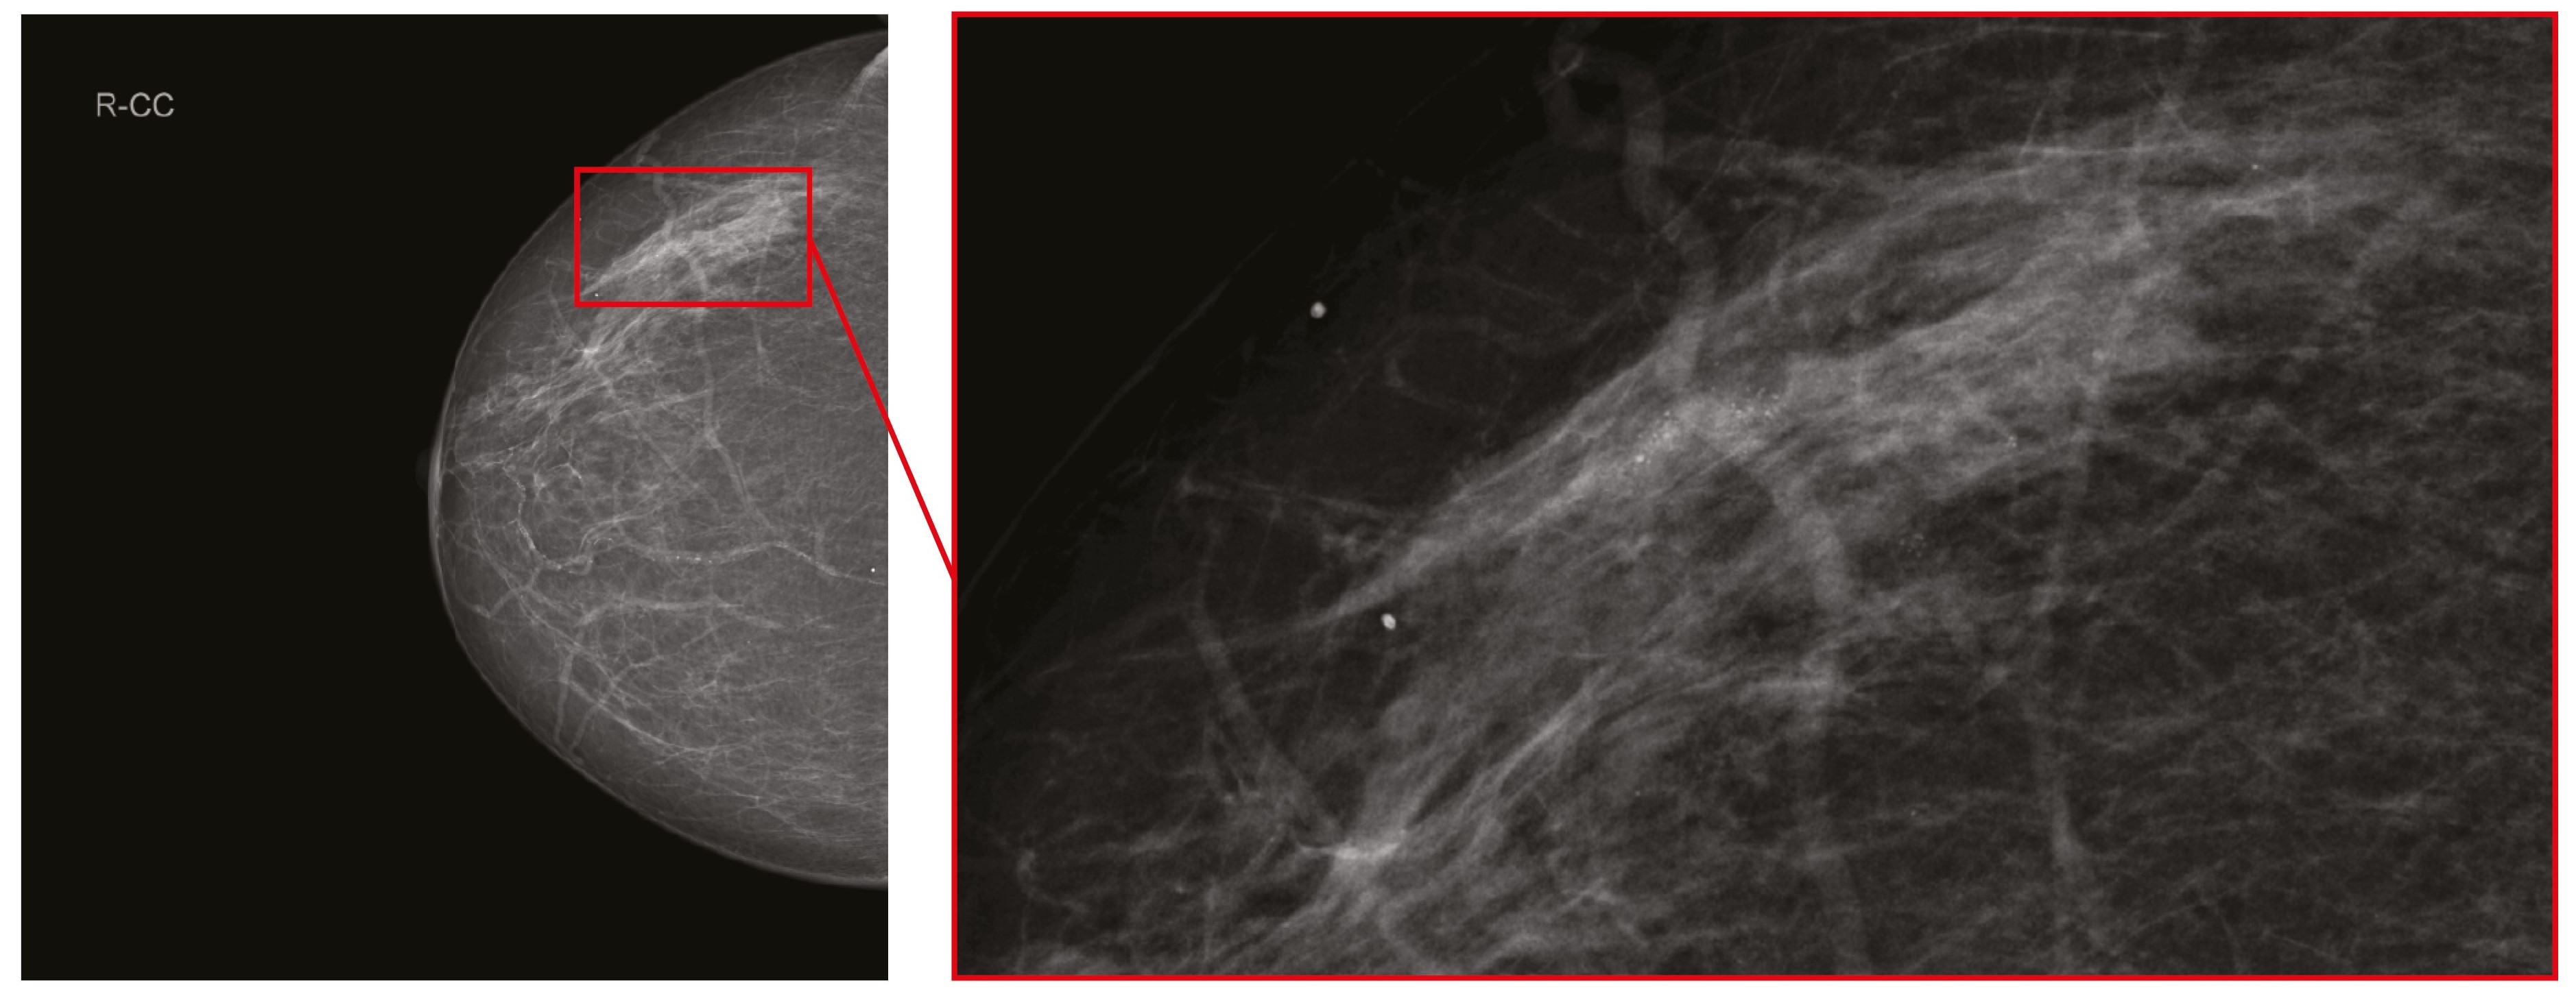

Однако присутствовали и единичные случаи значимого расхождения в оценках маммографических исследований. В одном из таких случаев рентгенолог, выполнивший первичное описание, и врачи, выполнившие пересмотр, обратили внимание на очаговое скопление микрокальцинатов в паренхиме правой молочной железы (рис. 1). Все врачи оценили изменения как соответствовавшие категории BI-RADS 4. Не исключено, что выявленная патология в правой молочной железе повлияла на оценку левой молочной железы у той же пациентки, где двое рентгенологов распознали в указанной на рис. 2 зоне интереса очаговое скопление микрокальцинатов и определили категорию BI-RADS 4, тогда как остальные врачи интерпретировали изменения как линейную фрагментарную кальцинацию в проекции стенки сосуда и установили категорию BI-RADS 2.

Рис. 1. Правая молочная железа в краниокаудальной проекции с выделенной областью интереса. Очаговое скопление микрокальцинатов в паренхиме правой молочной железы